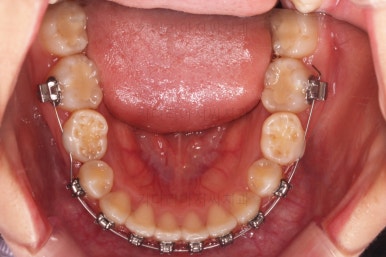

초진 때의 입안 모습입니다.

원래 다니던 치과에서 1년여 교정치료를 진행하신 상태였는데요.

몇 가지 이상한 점이 보이죠?

한 쪽만 발치가 되어있다.

아랫니에 유치가 2개가 그대로 남아있다.(화살표)

몇몇 이아에는 장치가 부착되어 있지 않다.